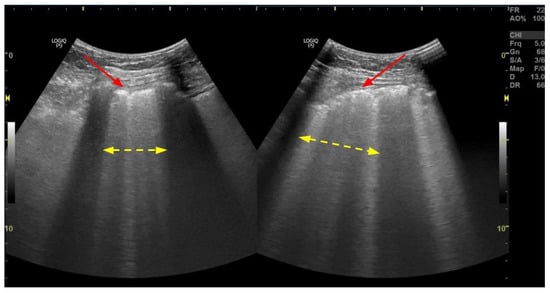

3.3. Pleural Effusion